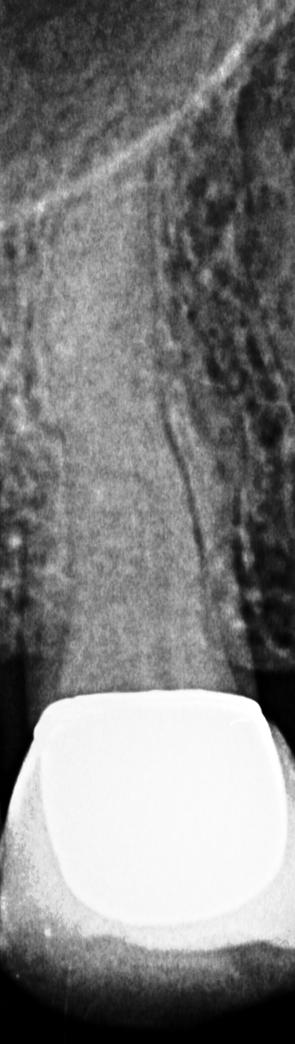

02 AusgangsaufnahmeEinzeln

Durchblick